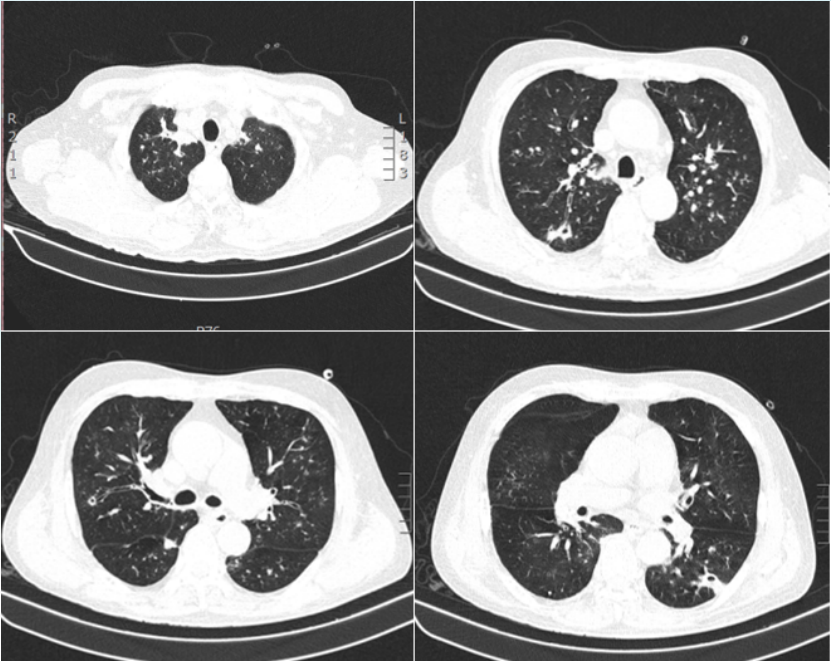

6月20日,待患者情况稳定后复查胸部CT:较6月6日出现新的病变(图12)。再次启动两性霉素B胆固醇酯质复合物(50~100~150 mg/d)抗真菌,同时予头孢哌酮舒巴坦+多黏菌素B(静脉+雾化)抗细菌治疗。

图片

12  患者胸部CT(2023-06-20)